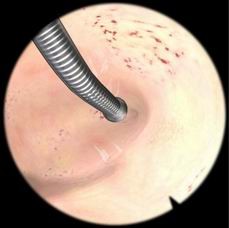

肌瘤切除模块

病例由易到难,简单的病例可发生在子宫底部,复杂的病例可发生在子宫前壁或者靠近输卵管口的地方

息肉切除模块